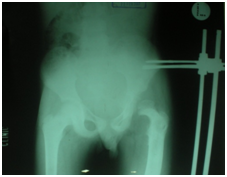

Figure 1 Initial radio graph- Femoral head dislocated supra-laterally, Shaper cook deformity of left femoral cortices are sclerosed, a large hyper dense area in the medullary cavity sequestrum. Pelvis tilted on the right.